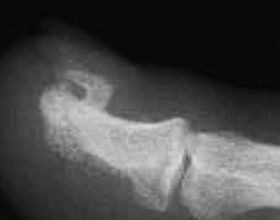

Az oszteokondromatózis diagnózisának alapja ma is a hagyományos röntgenfelvétel. Többszörös oszteokondróma felfedezése után egésztest CT vagy MRI javasolt az összes keletkezett daganat elhelyezkedésének és nagyságának meghatározására. A csigolyák és a medencecsontok daganatainak pontos feltérképezése csak rétegvizsgálattal (CT, MRI) lehetséges.

A diagnosztikában a röntgenfelvétel jellegzetes képet mutat: a csontkéreg és a velőűr folytonosan áthúzódik a kinövésbe, ami segít elkülöníteni más csontfelszíni elváltozásoktól. MRI vizsgálat különösen akkor hasznos, ha a porcborítás vastagságát szeretnénk megítélni, vagy ha lágyrész-érintettség merül fel. Gyermekkorban törekedni kell a sugárterhelés minimalizálására, ezért az ismételt CT-vizsgálat csak indokolt esetben javasolt.